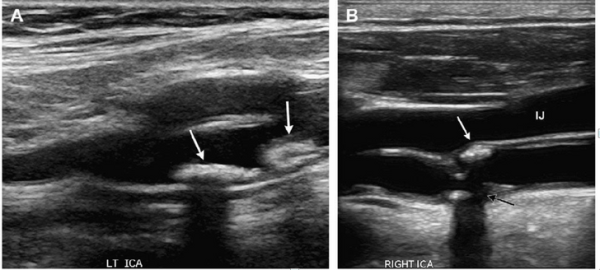

Однако эксперты уверяют: высокий холестерин и наличие бляшек по внешнему виду плазмы не увидеть. А вот что наглядно показывает атеросклероз, так это снимки УЗИ сосудов.

На кадрах ниже стрелочками показаны бляшки, которые перекрывают просветы сосудов. Еще немного — и они могут полностью закупорить сосуд, что грозит страшными последствиями.